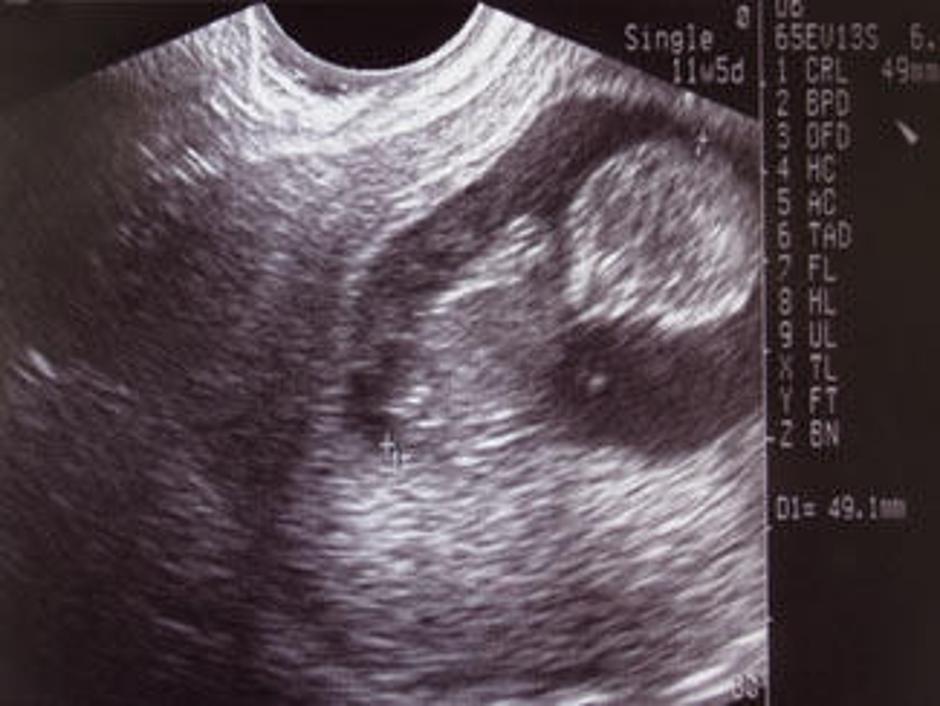

ultrazvok plod Slovenija Uzakonili pravico do pokopa splavljenih otrok